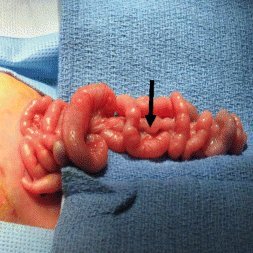

Ileal Atresia

Jejunal Atresia